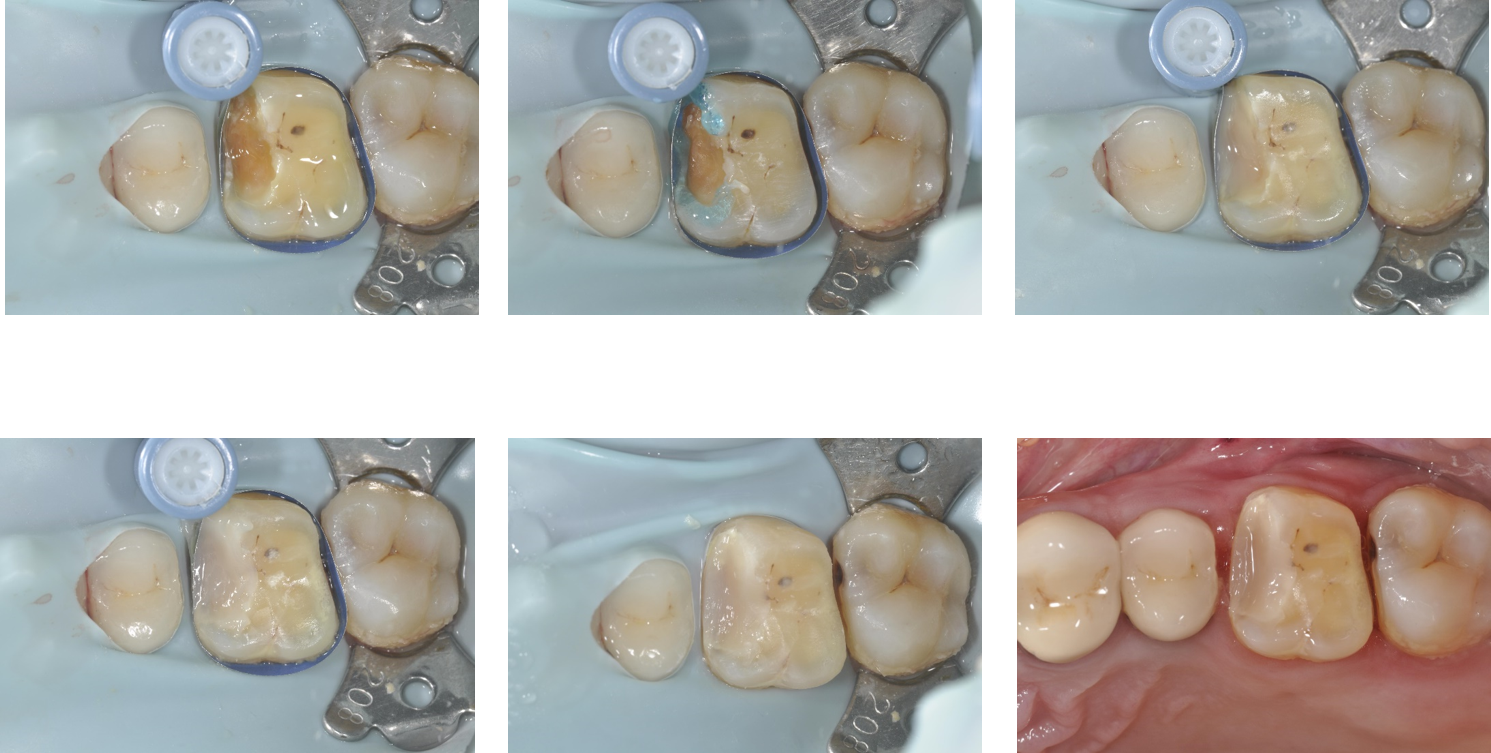

將牙齦下蛀牙移除並預填補

陶瓷冠塊體製備後

印模後,上咬合器

模型製作